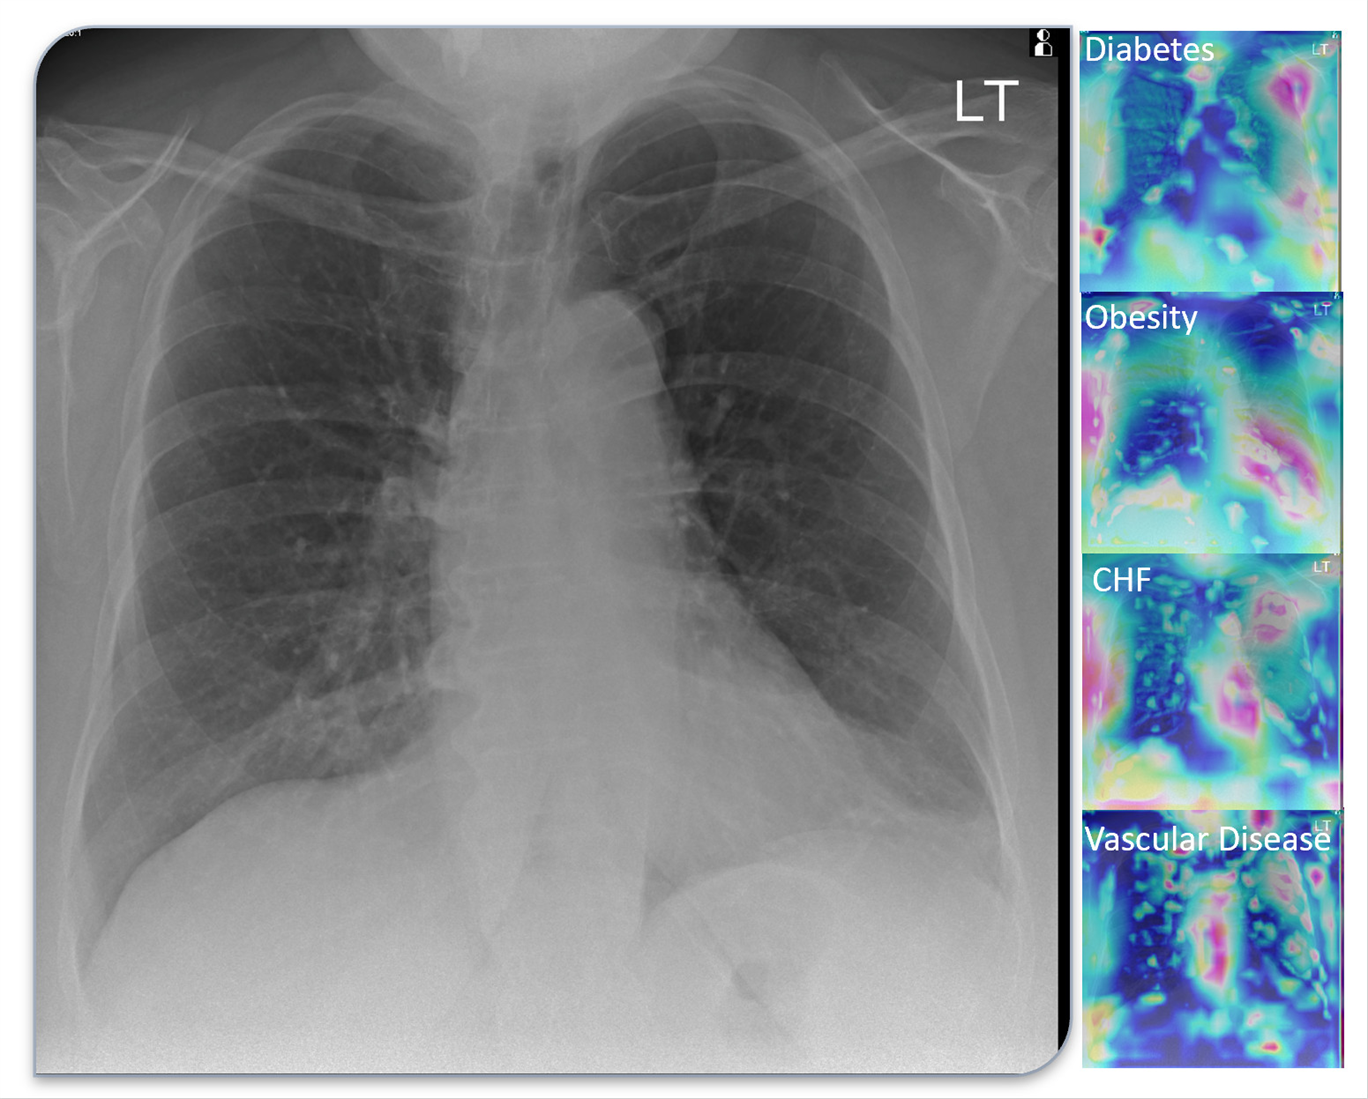

The tool they have created uses AI to evaluate an X-ray and account for six health variables. Typically, Dr. Pyrros said, radiologists focus on the lungs. Their program accounts for diabetes and other chronic conditions to more accurately predict the severity of a patient’s COVID-19 case.

Lung scans from a COVID-19 patient.

Specifically, the AI reads an X-ray and accounts for six medical variables, including:

• Diabetes with chronic complications

• Obesity, or a BMI over 40

• Congestive heart failure, or an enlarged heart on the X-ray

• Cardiac arrhythmia, such as atrial fibrillation

• Vascular disease, including atherosclerosis, calcifications, plaques, etc.

• Lung disease, such as COPD